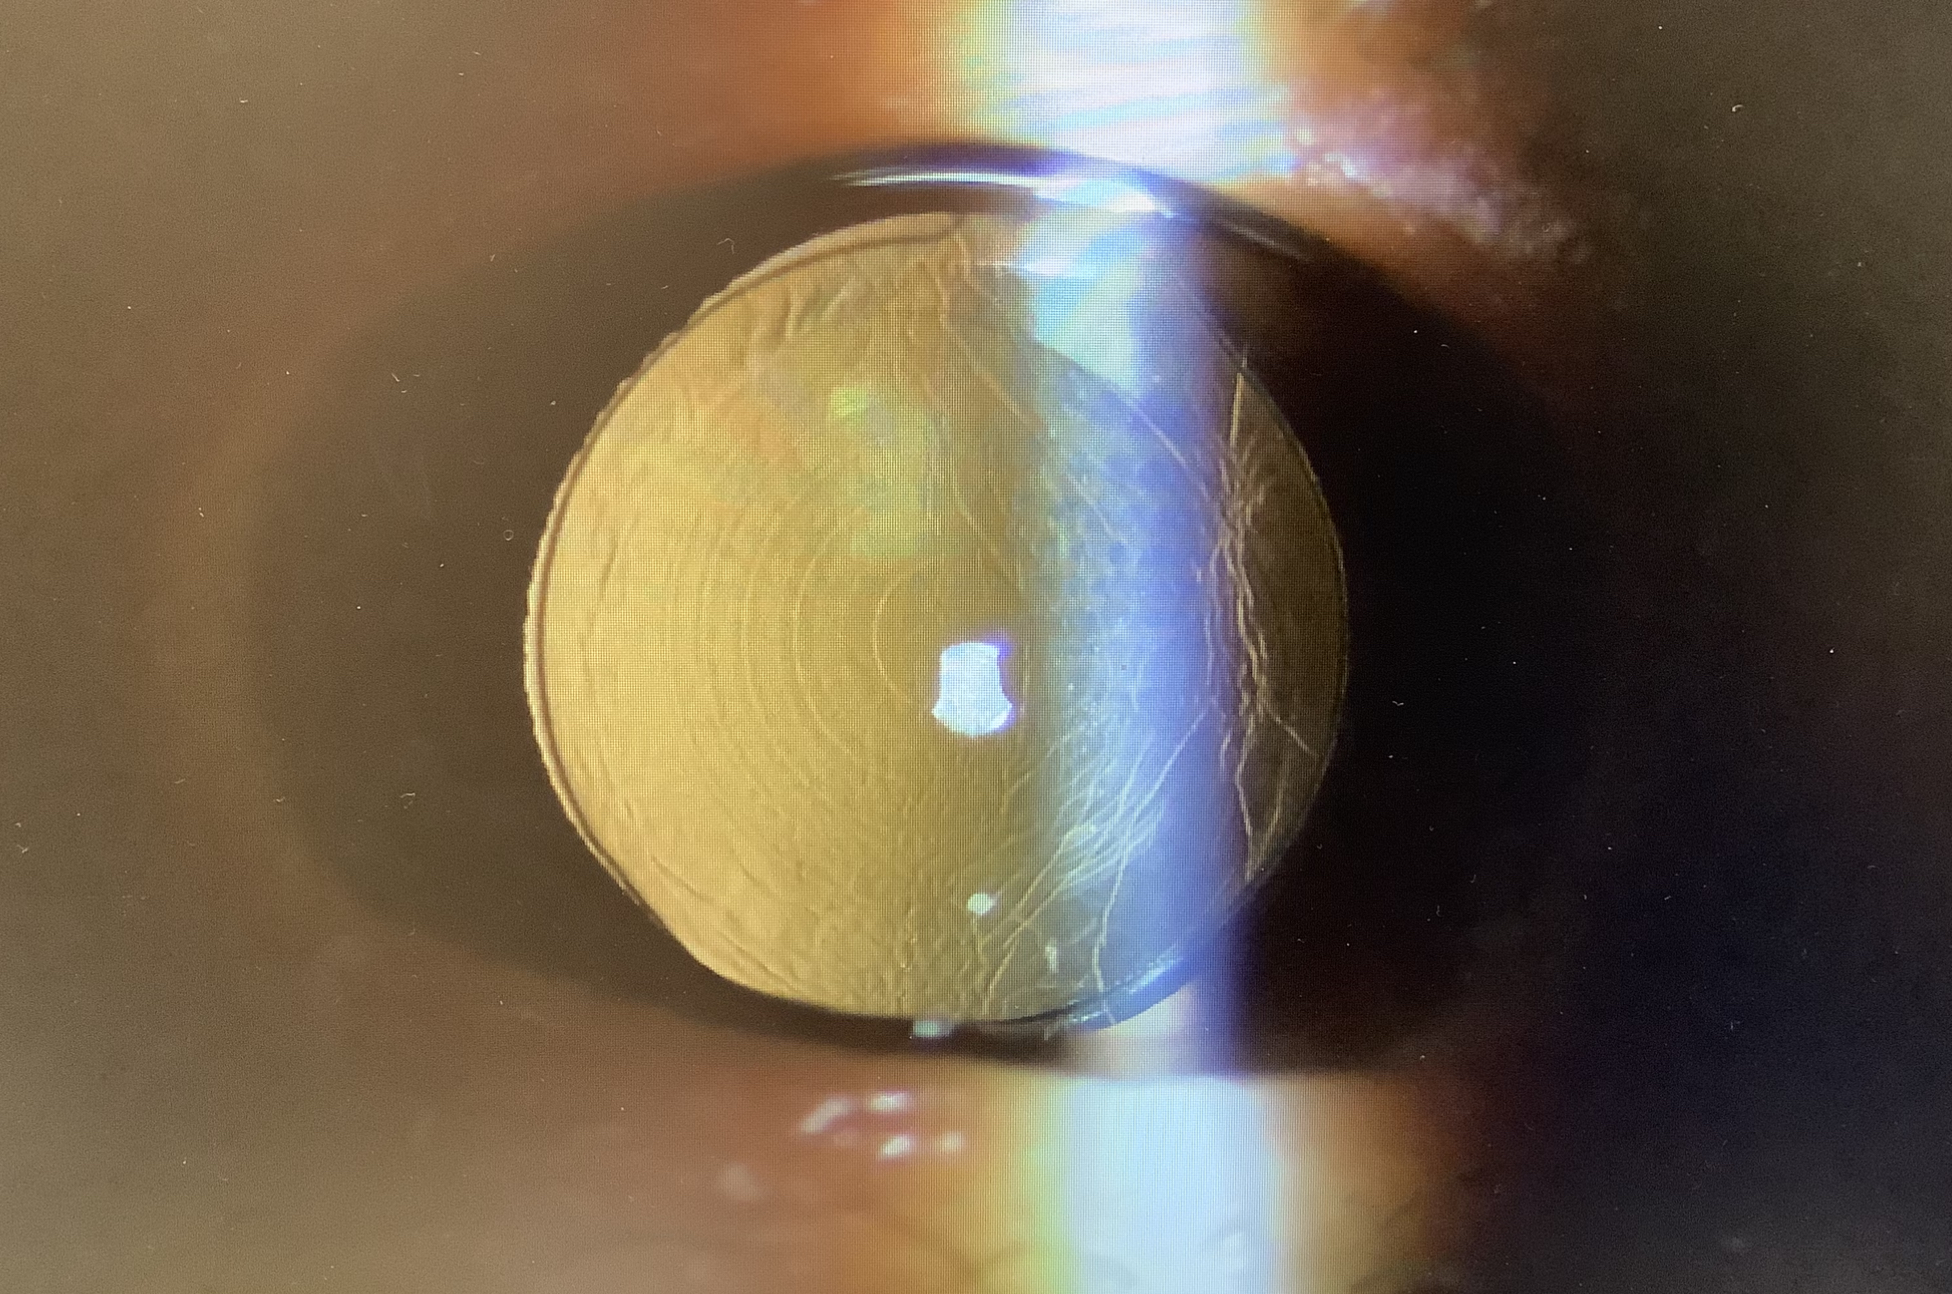

4月に当院で両眼ともVivityを使った白内障手術を行わせていただいた50代後半女性の方が、『近くが見えにくくて、5焦点レンズに入れ換えたい』ということでしたが、海外輸入レンズのため、手術日は2か月くらい先になるとお話したところ、早く手術してもらえるところがあると、5月下旬に他院で右眼の入れ換えを結局、パンオプティクスで行い、『近くも遠くも余計見えにくい』といらっしゃいました。レンズの特性上、Vivityよりはパンオプティクスの方が基本的に近くは見えるようになります。レンズもきれいに入っていますし、度数計算もバッチリでしたが、本人的に見えにくいと感じているのは、パンオプティクスの方がコントラストがやや下がるので、全体的なスッキリ感は多少下がったように感じている可能性はありますが、おそらくは後発白内障の影響と思われました。通常、後発白内障はゆっくり進むことが多いですが、レンズの入れ換えをすると、急激に進むことがたまにあります。それほど強い後発白内障でもないのではっきりしたことは言えず、しばらくは様子を見ることになりますが、実際に見えにくさの原因が後発白内障であれば、時間の経過で更に見えにくさが進むので、それが判断の基準になるかと思います。もちろん、後発白内障はレーザーで濁りを取り除いてしまえば、見やすくなるので、その治療をすることで原因がはっきりしますが、後嚢を破ってしまうと、レンズの入れ換えが困難になってしまうので、YAGレーザーの治療をする判断は慎重にする必要がありますし、もしYAGレーザーをするとなっても、万が一のレンズ交換に備えて、後嚢の切開は少し小さめに行うことが大事かと思っています。